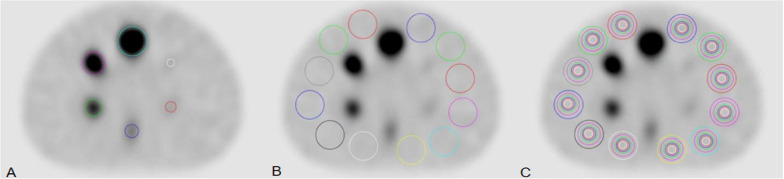

Methods: This study was composed of a phantom study and two clinical tests. The differences in visual image quality scores, coefficient of variance (COV) of the background, image signal-to-noise ratio (SNR), contrast-to-noise ratio (CNR), and recovery coefficient (RC) of the sphere were compared between SSC mode and traditional Step-and-Shoot (SS) mode in the phantom study. Various "shoot" acquisition times (5s, 10s, 15s) and "step" angles (3-degree, 6-degree, 9-degree) were evaluated and verified. In the clinical tests, bone tomography and parathyroid tomography were performed on 30 patients each. Differences in visual image quality scores, background COV, image SNR, CNR, and standardized uptake value (SUV) of lesions were compared between the two modes.

Results: In the phantom study, SSC mode demonstrated higher visual scores and significantly reduced background COV (P < 0.05), and significantly increased SNR and CNR (P < 0.05) compared to SS mode. No significant alteration in RC was observed (P > 0.05). In the clinical tests, no significant differences were found between the optimal SSC scan combination (10s "shoot" and 6-degree "step")/ (10s "shoot" and 3-degree "step") and the traditional SS scan combination (15s "shoot" and 6-degree "step")/ (15s "shoot" and 3-degree "step") in visual image quality scores, background COV, image SNR, CNR, and SUV of bone and parathyroid high uptake lesions (P > 0.05).